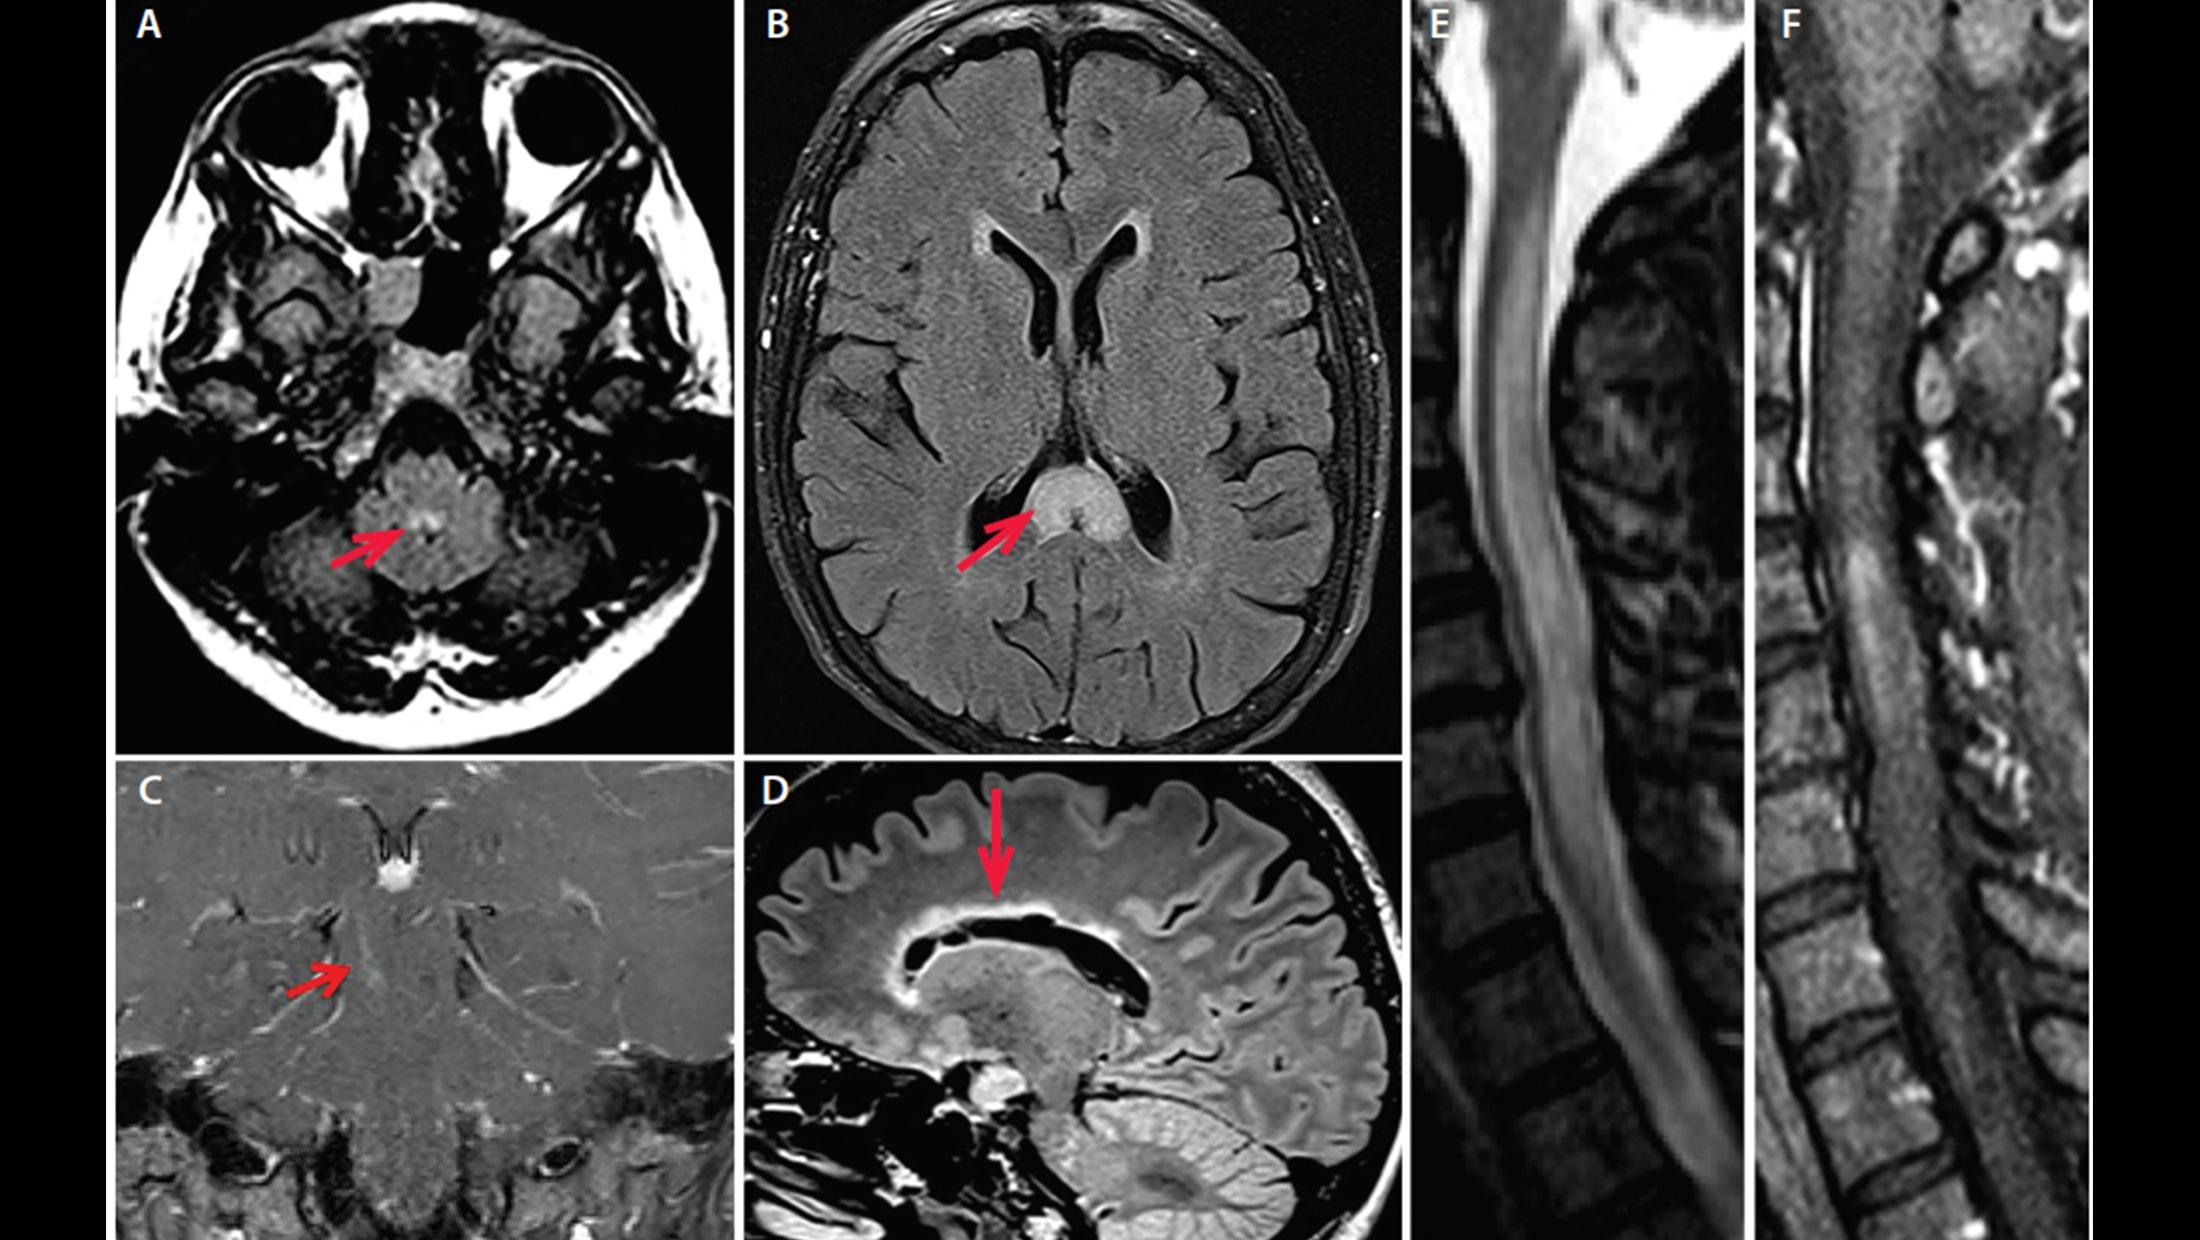

發現後緊急會診過敏免疫風濕科許寶寶醫師加入生物製劑的治療,降低嚴重程度及復發機率。許寶寶醫師說,在核磁共振檢查中,神經內科發現病人有縱向性脊椎炎,從頸椎的第7節到腰椎的第10節,加上aquaporin-4(AQP4)抗體(NMO-IgG)檢測為陽性,確認是罕見的泛視神經脊髓炎合併乾燥症,即開始積極使用類固醇脈衝跟血漿置換術為她治療,約1至2個月後,神經開始修復。王女士形容,神經修復期間,只要翻身就痛如刀割又如火燒,心情低落到想自殺。